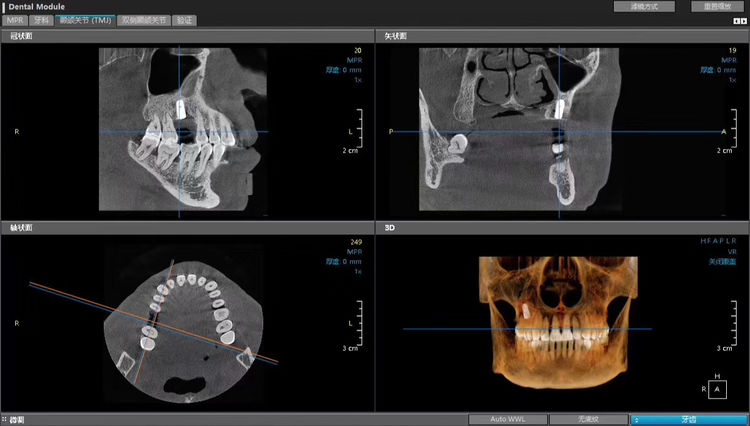

kavo齿科锥形束CT

三维分析

模拟种植牙数据